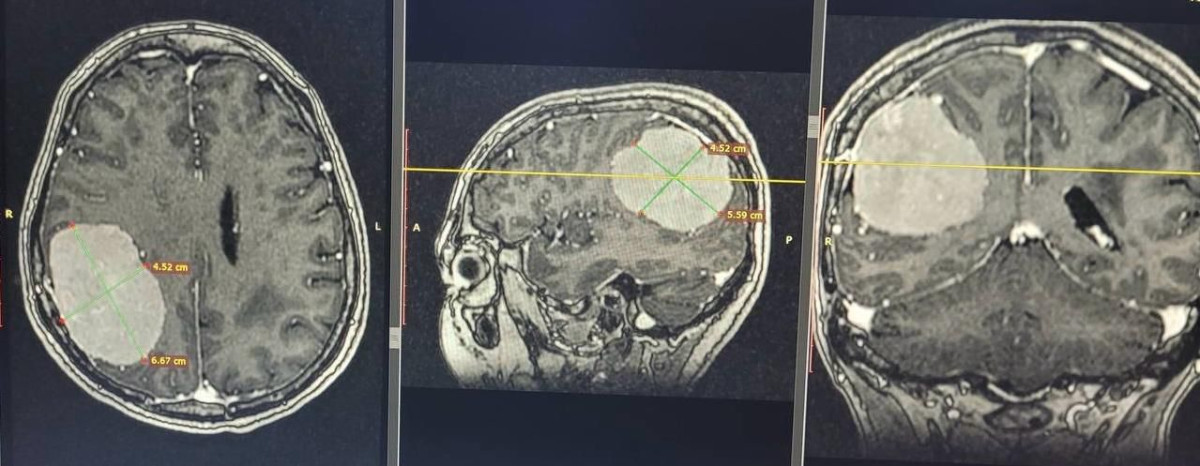

Вероятно образование медленно росло и в итоге достигло 7-8 сантиметров.

"Пациентке срочно провели двухэтапную операцию. Сначала ведущий нейрохирург страны Мынжылкы Бердиходжаев эмболизировал все питающие сосуды нароста, чтобы уменьшить кровопотерю, а затем нейрохирург Шаяхмет Маханбетулы и команда его отделения удалили женщине опухоль тотально. Операция длилась шесть с половиной часов, она относится к одним из сложнейших, но в итоге всё прошло успешно. Сейчас женщина восстанавливается в отделении нейрохирургии, уже готовится к выписке", – отмечается в пресс-релизе.